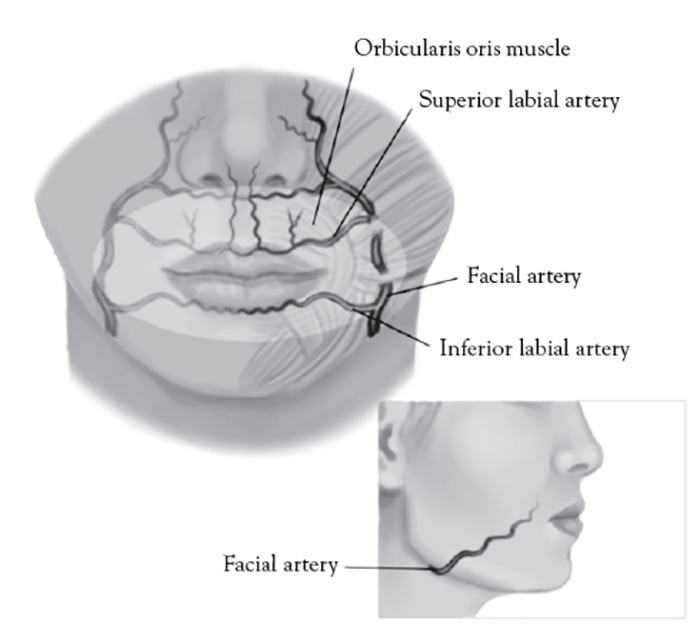

The facial artery is a branch of the external carotid artery, emerging superficial to the posterior belly of the digastric muscle, stylohyoid muscle, and submandibular gland, and coursing in a continuous oblique plane (1.5 cm)from the lateral commissure of the mouth to nasal ala along the lateral border of the nasolabial fold [146]. Proper injection technique for injecting cosmetic filler to the nasolabial fold is medial and very superficial, targeting the lower two-thirds intradermal plane, avoiding the nasal ala, where facial artery is most superficial [147].Inadvertent direct subcutaneous intravascular facial artery injection and/or compressive ischemia in the upper third of the nasolabial fold can result in an ocular embolism, blindness, and necrosis of the alar and malar region of the nose and cheek [148]. The facial artery is visible with color Doppler ultrasound when using proper technique (Figure 9).

The facial artery is located 15 mm lateral to the lip commissure and divides into the superior labial artery in the upper lip and inferior labial artery of the lower lip (Figure 10). These arteries are typically deep and run between the orbicularis oris muscle and oral mucosa [149]. General rules when addressing this facial area are [20,149]:

Always inject superficially and low-pressure injection

Never inject deeper than 3 mm from the skin or vermillion border (avoiding muscle)

Stay within a thumb width of the lip commissure

Inject slowly using retrograde technique

In addition, one should avoid the interior of the Cupid's bow, the orphiltrum [20,149]. The labial arteries are too small in caliber and not amenable to conventional color Doppler ultrasound not otherwise equipped with power Doppler capability.